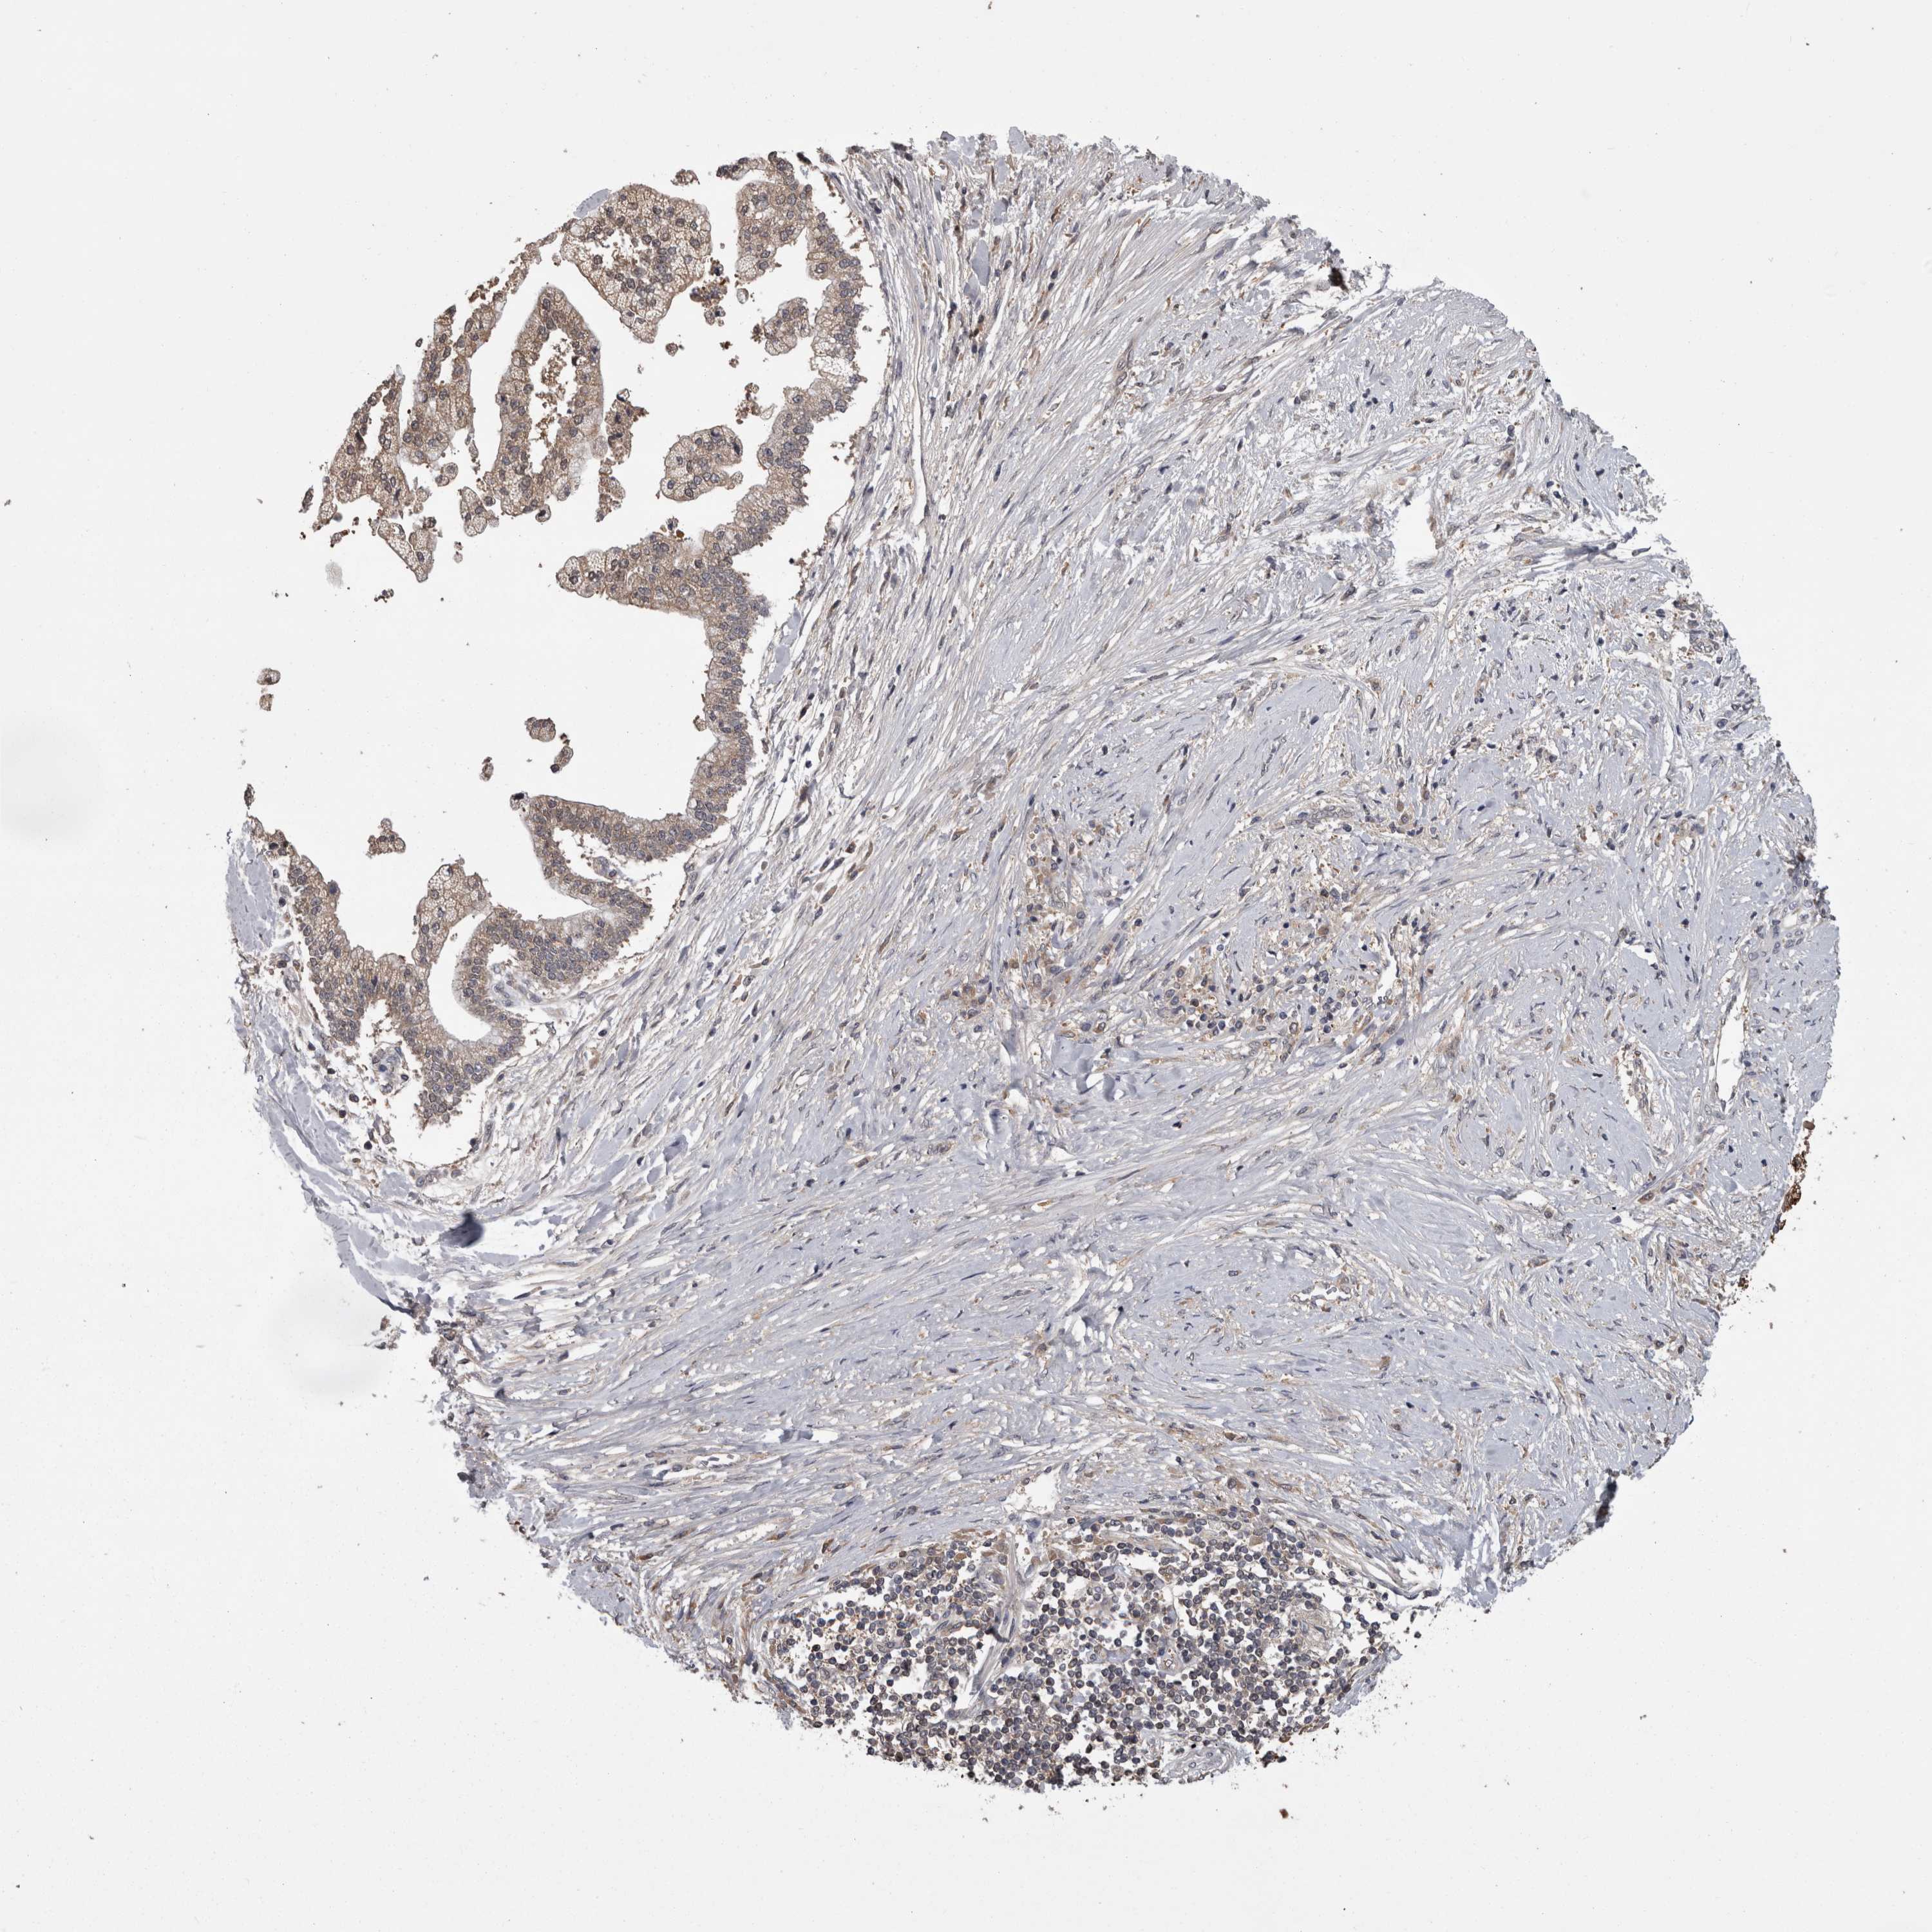

LIVER CANCER - Protein expressioni

A mouse-over function shows sample information and annotation data. Click on an image to view it in a full screen mode. Samples can be filtered based on level of antibody staining by selecting one or several of the following categories: high, medium, low and not detected. The assay and annotation is described here.

Note that samples used for immunohistochemistry by the Human Protein Atlas do not correspond to samples in the TCGA dataset.

Antibody stainingi

Antibody staining in the annotated cell types in the current human tissue is reported as not detected, low, medium, or high, based on conventional immunohistochemistry profiling in selected tissues. This score is based on the combination of the staining intensity and fraction of stained cells.

Each image is clickable and will lead to virtual microscopy that enables deeper exploration of all samples and also displays staining intensity scores, fraction scores and subcellular localization as well as patient and tissue information for each sample.

Antibody HPA026681

Staining

High

Medium

Low

Not detected

Intensity

Strong

Moderate

Weak

Negative

Quantity

>75%

75%-25%

<25%

None

Location

Nuclear

Cytoplasmic/membranous

Cytoplasmic/membranous,nuclear

Cholangiocarcinoma

Carcinoma, Hepatocellular, NOS